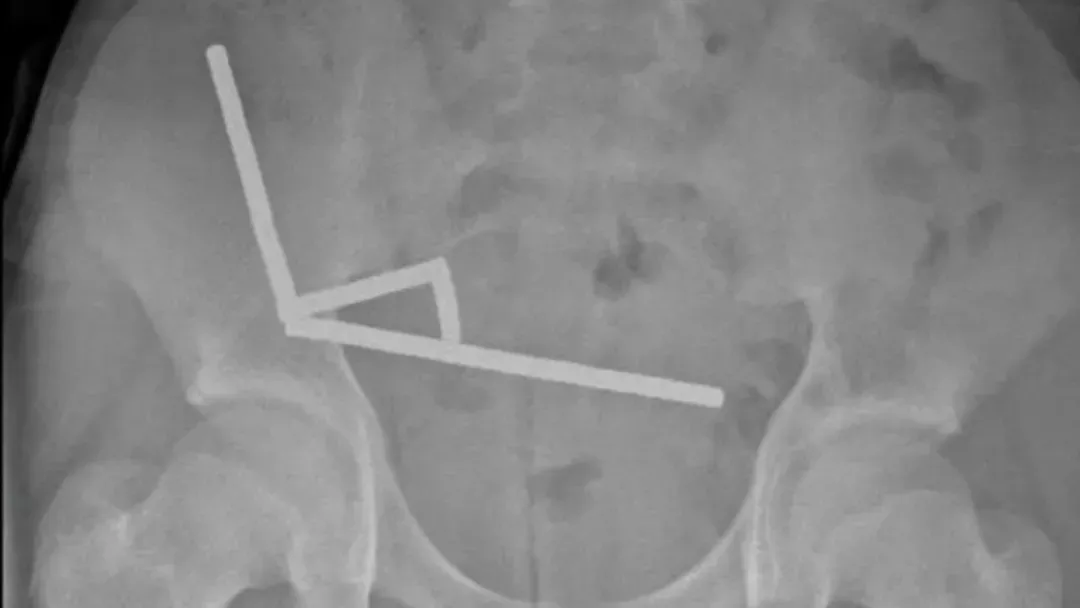

医生通过 X 光片观察到,男孩肠道的不同部位出现了四条线状的磁铁链。

腹部 X 光片显示了磁铁分布情况 来源:Lekamalage et al.,?NZMJ, 2025